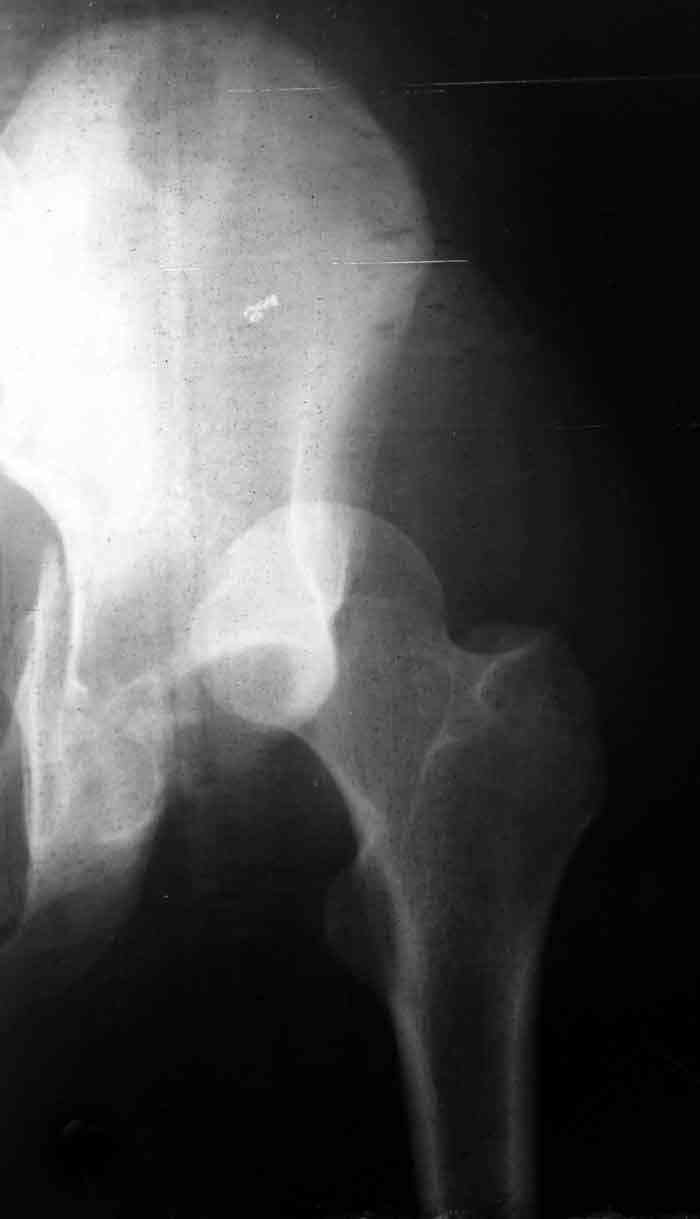

This is a 20 year old man who had an irreducible fracture dislocation of the left acetabulum, associated transverse + posterior wall type, operated nearly 2 weeks following the trauma.

Open reduction and internal fixation was performed through posterior approach with trochanteric osteotomy. Extraction of the incarcerated fragment was very difficult, and then reduction of the femoral head also felt less easy than usual. After plate fixation, the head was found to subluxe on maximum internal rotation. However, it became more or less stable after fixation of the trochanteric osteotomy and reattachment of the rotators. Xray showed lateral displacement of the femoral head. CT was also performed and it confirmed the lateral displacement although I don't know if it could be termed subluxation. The flexion- extension ROM is 0-45 with some internal-external rotation, but the limitation is mostly by pain. I cannot explain this situation and would you like to hear your suggestions.

I am confident that I left no intraarticular fragments. Could the comminution in the anterior wall visible on CT be responsible for this?